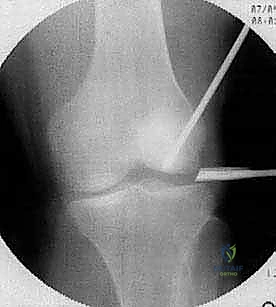

1. تقنية التثقيب أو الكسور الدقيقة (Microfracture / Drilling)

- الهدف: تحفيز نخاع العظم لإنتاج غضروف بديل.

- كيفية الإجراء: باستخدام المنظار، يقوم الدكتور هطيف بتنظيف المنطقة التالفة من الغضروف، ثم يستخدم أداة دقيقة لإحداث ثقوب صغيرة في العظم تحت الغضروفي المكشوف. هذه الثقوب تسمح بخروج الدم والخلايا الجذعية من نخاع العظم لتشكيل جلطة دموية (Super Clot) فوق المنطقة المصابة. بمرور الوقت، تتحول هذه الجلطة إلى نسيج ندبي يسمى "الغضروف الليفي" (Fibrocartilage).

- الاستطبابات: الآفات الصغيرة (أقل من 2-3 سم مربع)، والآفات المستقرة التي تحتاج إلى تحفيز التروية الدموية.

- الميزة: إجراء بسيط بالمنظار، فترة نقاهة أولية سريعة.